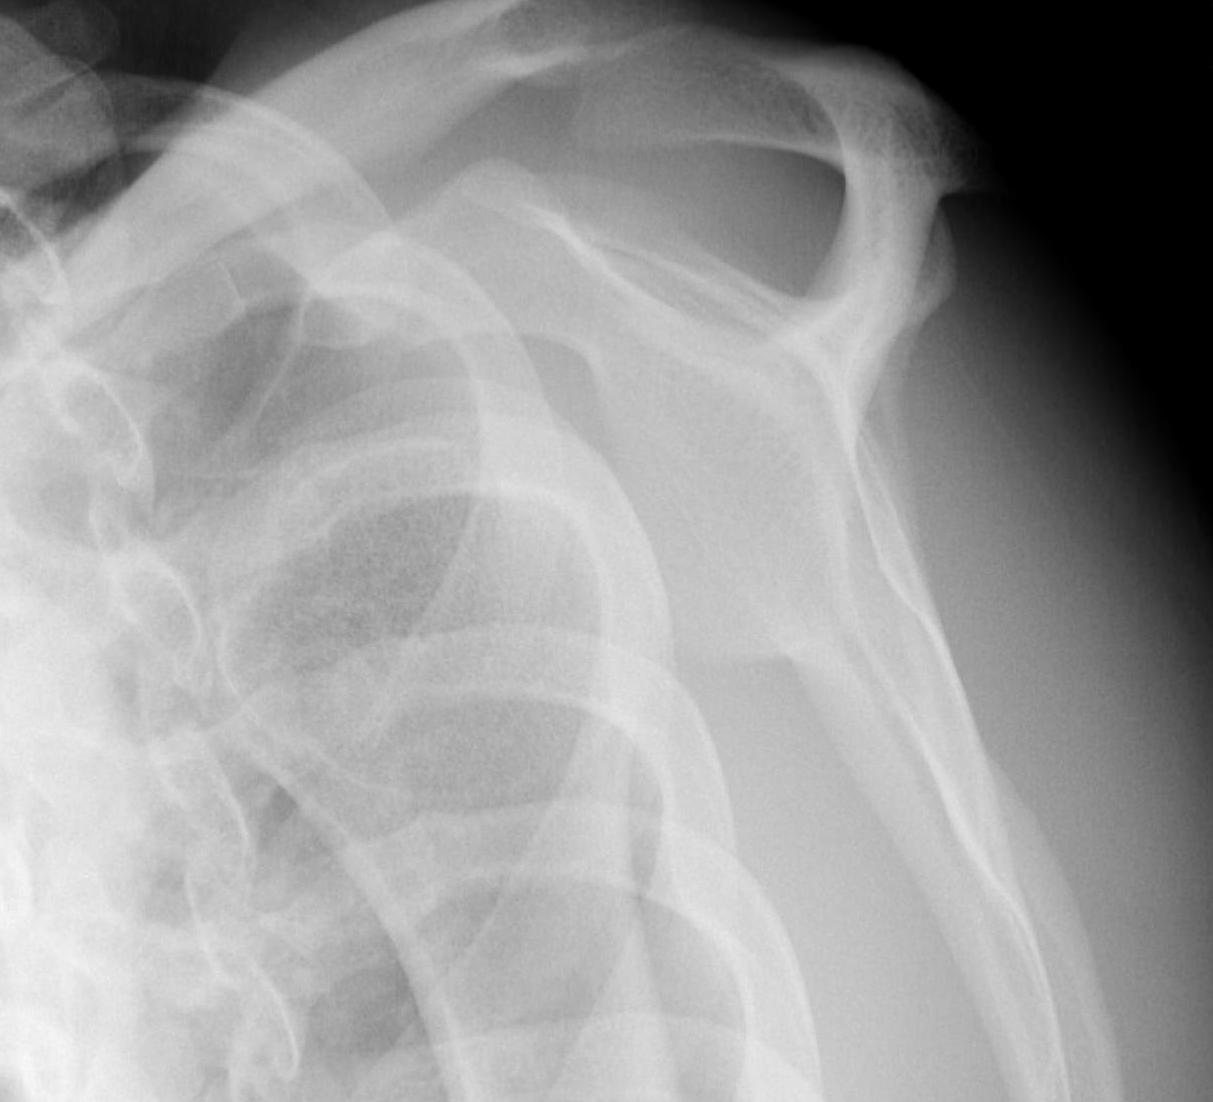

Rotator Cuff Tear

Infraspinatus and supraspinatus wasting after shoulder dislocation in 50 year old

More common in older patients with shoulder dislocation

- 66 patients > 50 with shoulder dislocation

- 60% rotator cuff tear on MRI